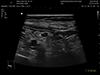

![]() |

Kidney & Adrenal Gland US 신장 및 부신 초음파 고해상도 초음파를 이용해 신장과 부신의 크기, 형태, 병변 유무를 실시간으로 관찰하여 신장 결석, 수신증, 종양, 부신 종괴 등 이상을 평가하는 검사입니다. |